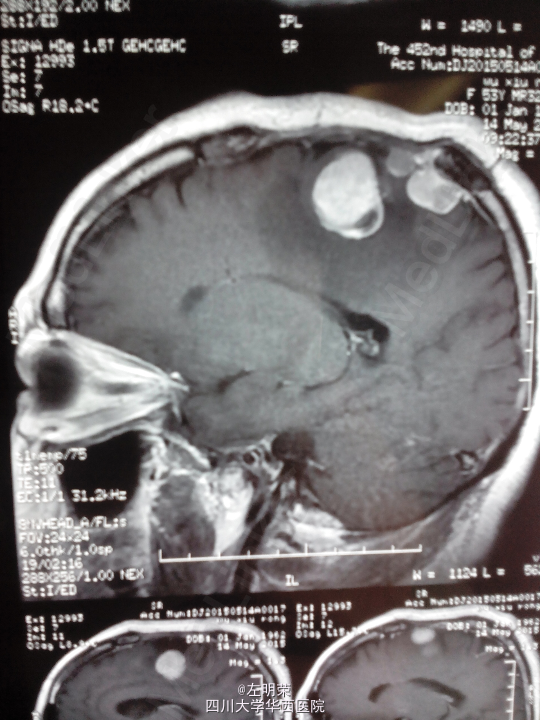

脑膜瘤术后复发(多发脑膜瘤)

左下肢乏力伴间断抽搐半年+, 患者于5年前行左侧额叶脑膜瘤切除术,术后行伽马刀治疗数次,近来出现肢体无力伴抽搐,不规律服用抗癫痫药物,昨日再发抽搐。

1、多发脑膜瘤 2、继发性癫痫

行占位切除术;待病理结果;术后应复查头部MRI,确定肿瘤切除情况,拟定下一步治疗方案。